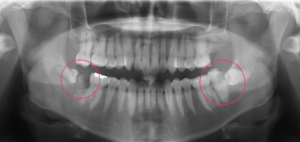

そのため抜歯前にはレントゲンや歯科用CTを撮影し、当院において抜歯が可能か判断させていただいています。抜歯が難しい場合やリスクが大きい場合は近くの大きい病院へ紹介させていただく場合もあります